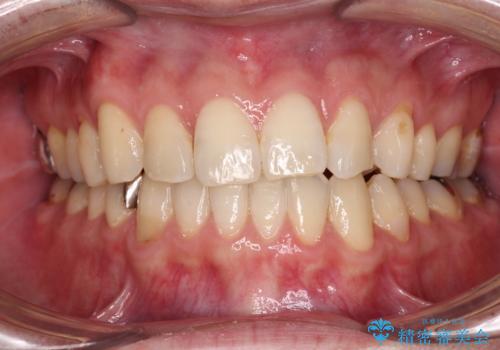

- デコボコした前歯をセラミックできれいに揃えたいとのことで来院された患者様です。

歯を削って整えることは簡単ですが、健全な歯を削って後悔してからでは遅いため、矯正治療を提案しました。

はじめは矯正治療の期間が長いことに悩んでいらっしゃいましたが、ある程度整えば満足するだろうとのことで、インビザラインにて矯正治療を行うこととしました。

左上の犬歯が欠損しているため、正中の位置や奥歯の咬み合わせが理想的にならない点を了承していただきました。

インビザライン矯正は、1日22時間を目安に装着する必要がありますが、しっかりと装着してくださったので、順調に治療を進めることができました。